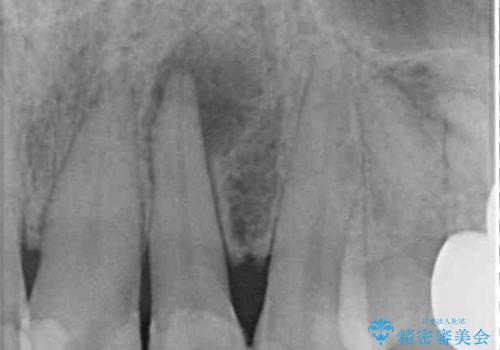

レントゲン写真から、大きくなった根尖病変が認められました。

根管治療後速やかに痛みが消退し、6ヶ月後のレントゲン写真では、根尖部の病変がほぼなくなっていることが分かりました。